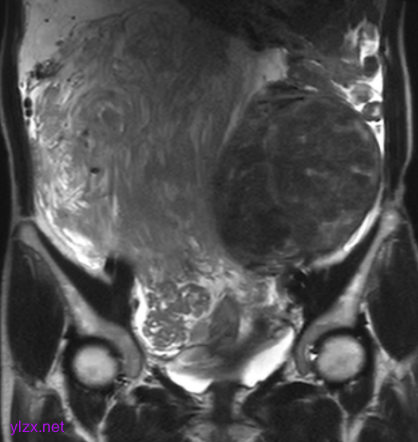

MRI检查:

子宫右侧巨大实性占位,大小约260×110×91mm,与子宫分界不清,T1WI呈稍低信号,T2WI呈不均匀稍高信号,呈束状、旋涡状改变(图1),病变内部分可见囊变,肿瘤内部及表面多发流空血管影(图2);DWI上病变呈略高信号,ADC图呈略低信号,ADC值为1.633×10-3 mm2 /s;增强扫描呈明显强化(图3),内部见条片状低信号。影像学考虑子宫右侧恶性肿瘤。

图1

子宫PEComa影像学表现各异,其MRI表现具有一定的特征,肿瘤T2WI信号稍高,呈束状排列,富血供,可伴有变性、坏死,肿瘤内部及表面可见多发流空血管影。